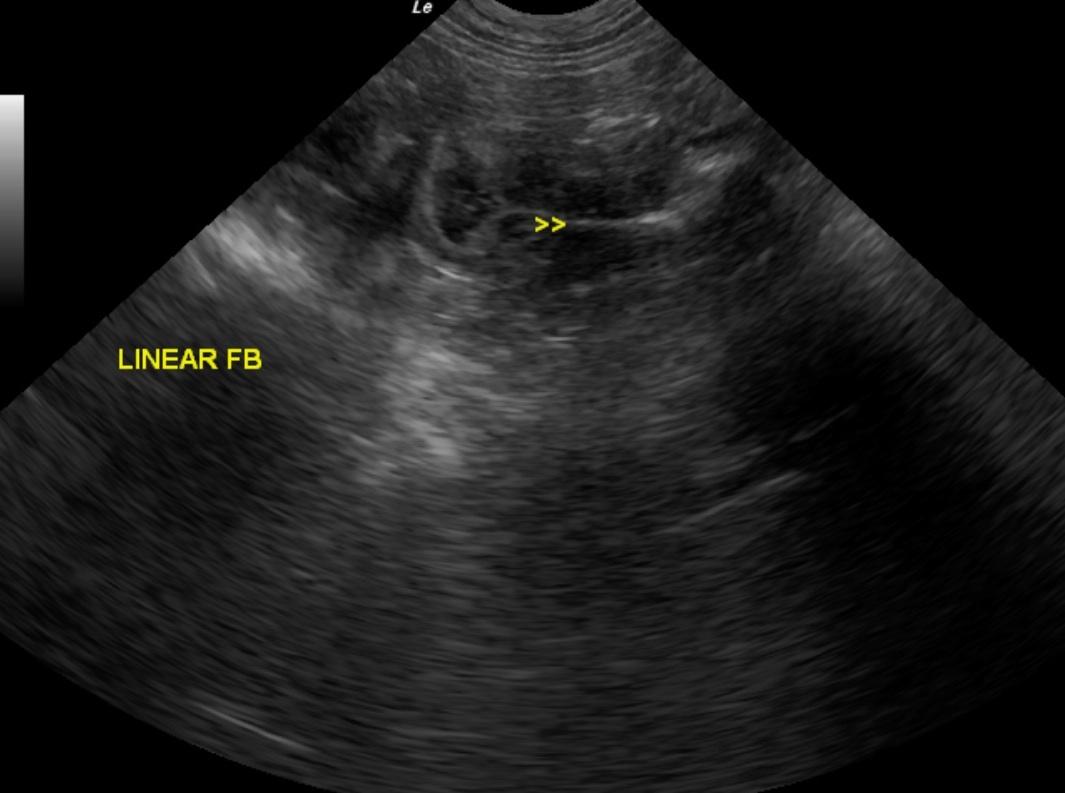

An 8-month old MN Cockapoo dog was presented with a history of vomiting, diarrhea, anorexia, lethargy, and painful abdomen. Leukocytosis was present on CBC, whereas serum biochemistry panel was within normal limits.